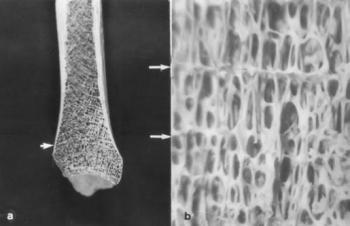

120. ábra. Mindkét tibia distalis végén jól látszanak a Harris-féle harántvonalak (nyíl)

A Harris-vonal a növekedésben lévők táplálkozási elégtelenségének következménye, az epiphysisben a csontosodási vonal időlegesen lezáródik, majd a megfelelő étkezésre való visszatéréskor a növekedés ettől distal felé folytatódik. A Harris-vonalak a gyermekek és felnőttek vázanyagán egyaránt kimutathatók. Nem feltétlenül utalnak éhezésre, jelezhetik a viszonylagos elégtelenséget, ugyanis a lázas betegségekben romlik a tápanyagok hasznosítása, miközben a szervezet fehérje, vitamin és kalóriaigénye fokozott. A Harris-vonalak elhelyezkedéséből következtetni lehet, hogy a nutricionális zavar milyen életkorban következett be, számukból pedig a malnutriciós időszakok ismétlődése mondható meg. Elsősorban a tibiában, a femurban és humerusban, ritkábban az alkar és fibula, kivételesen a kéz és lábközép csontokban képződhet. A recens populáció rtg-felvételeinek 1-5%-ában is látszik. Bugyi (1972) arra hívta fel a figyelmet, hogy a II. világháború idején világrajött gyermekekben gyakoribb, mint az 1938 előtt, illetve 1950 után születettekben. A Harris-vonalak röntgenvizsgálattal és a csont metszéslapján jól felismerhetők (120. ábra, 121. ábra). A Vörs-Papkerti B (9–13. század) és a Tiszafüred-Nagykenderföldek (10–12. sz.) temetők több mint 2000 hosszú csöves csontjának rtg-vizsgálatakor az előbbiben a tibiák 66%án, 6-10 (maximálisan 28-28), a tiszafürediben fele ilyen gyakoriságú Harris-vonalat észleltünk (Józsa és Pap 1989). A női csontokon mindkét lelőhelyen többször, viszont férfiakon (ha volt) nagyobb számban fordult elő. A Harris vonalak száma jól korrelált egyéb, ugyancsak táplálkozási zavarra utaló indikátorokkal (Józsa és Pap 1989, 1990).

121. ábra. a) A csont metszéslapján is leolvasható a Harris-vonalak száma b) A Harris-vonalak nagyított képe (nyíl). 10–12. század, adultus férfi Sztereómikroszkópos felvétel 20×nagyítás